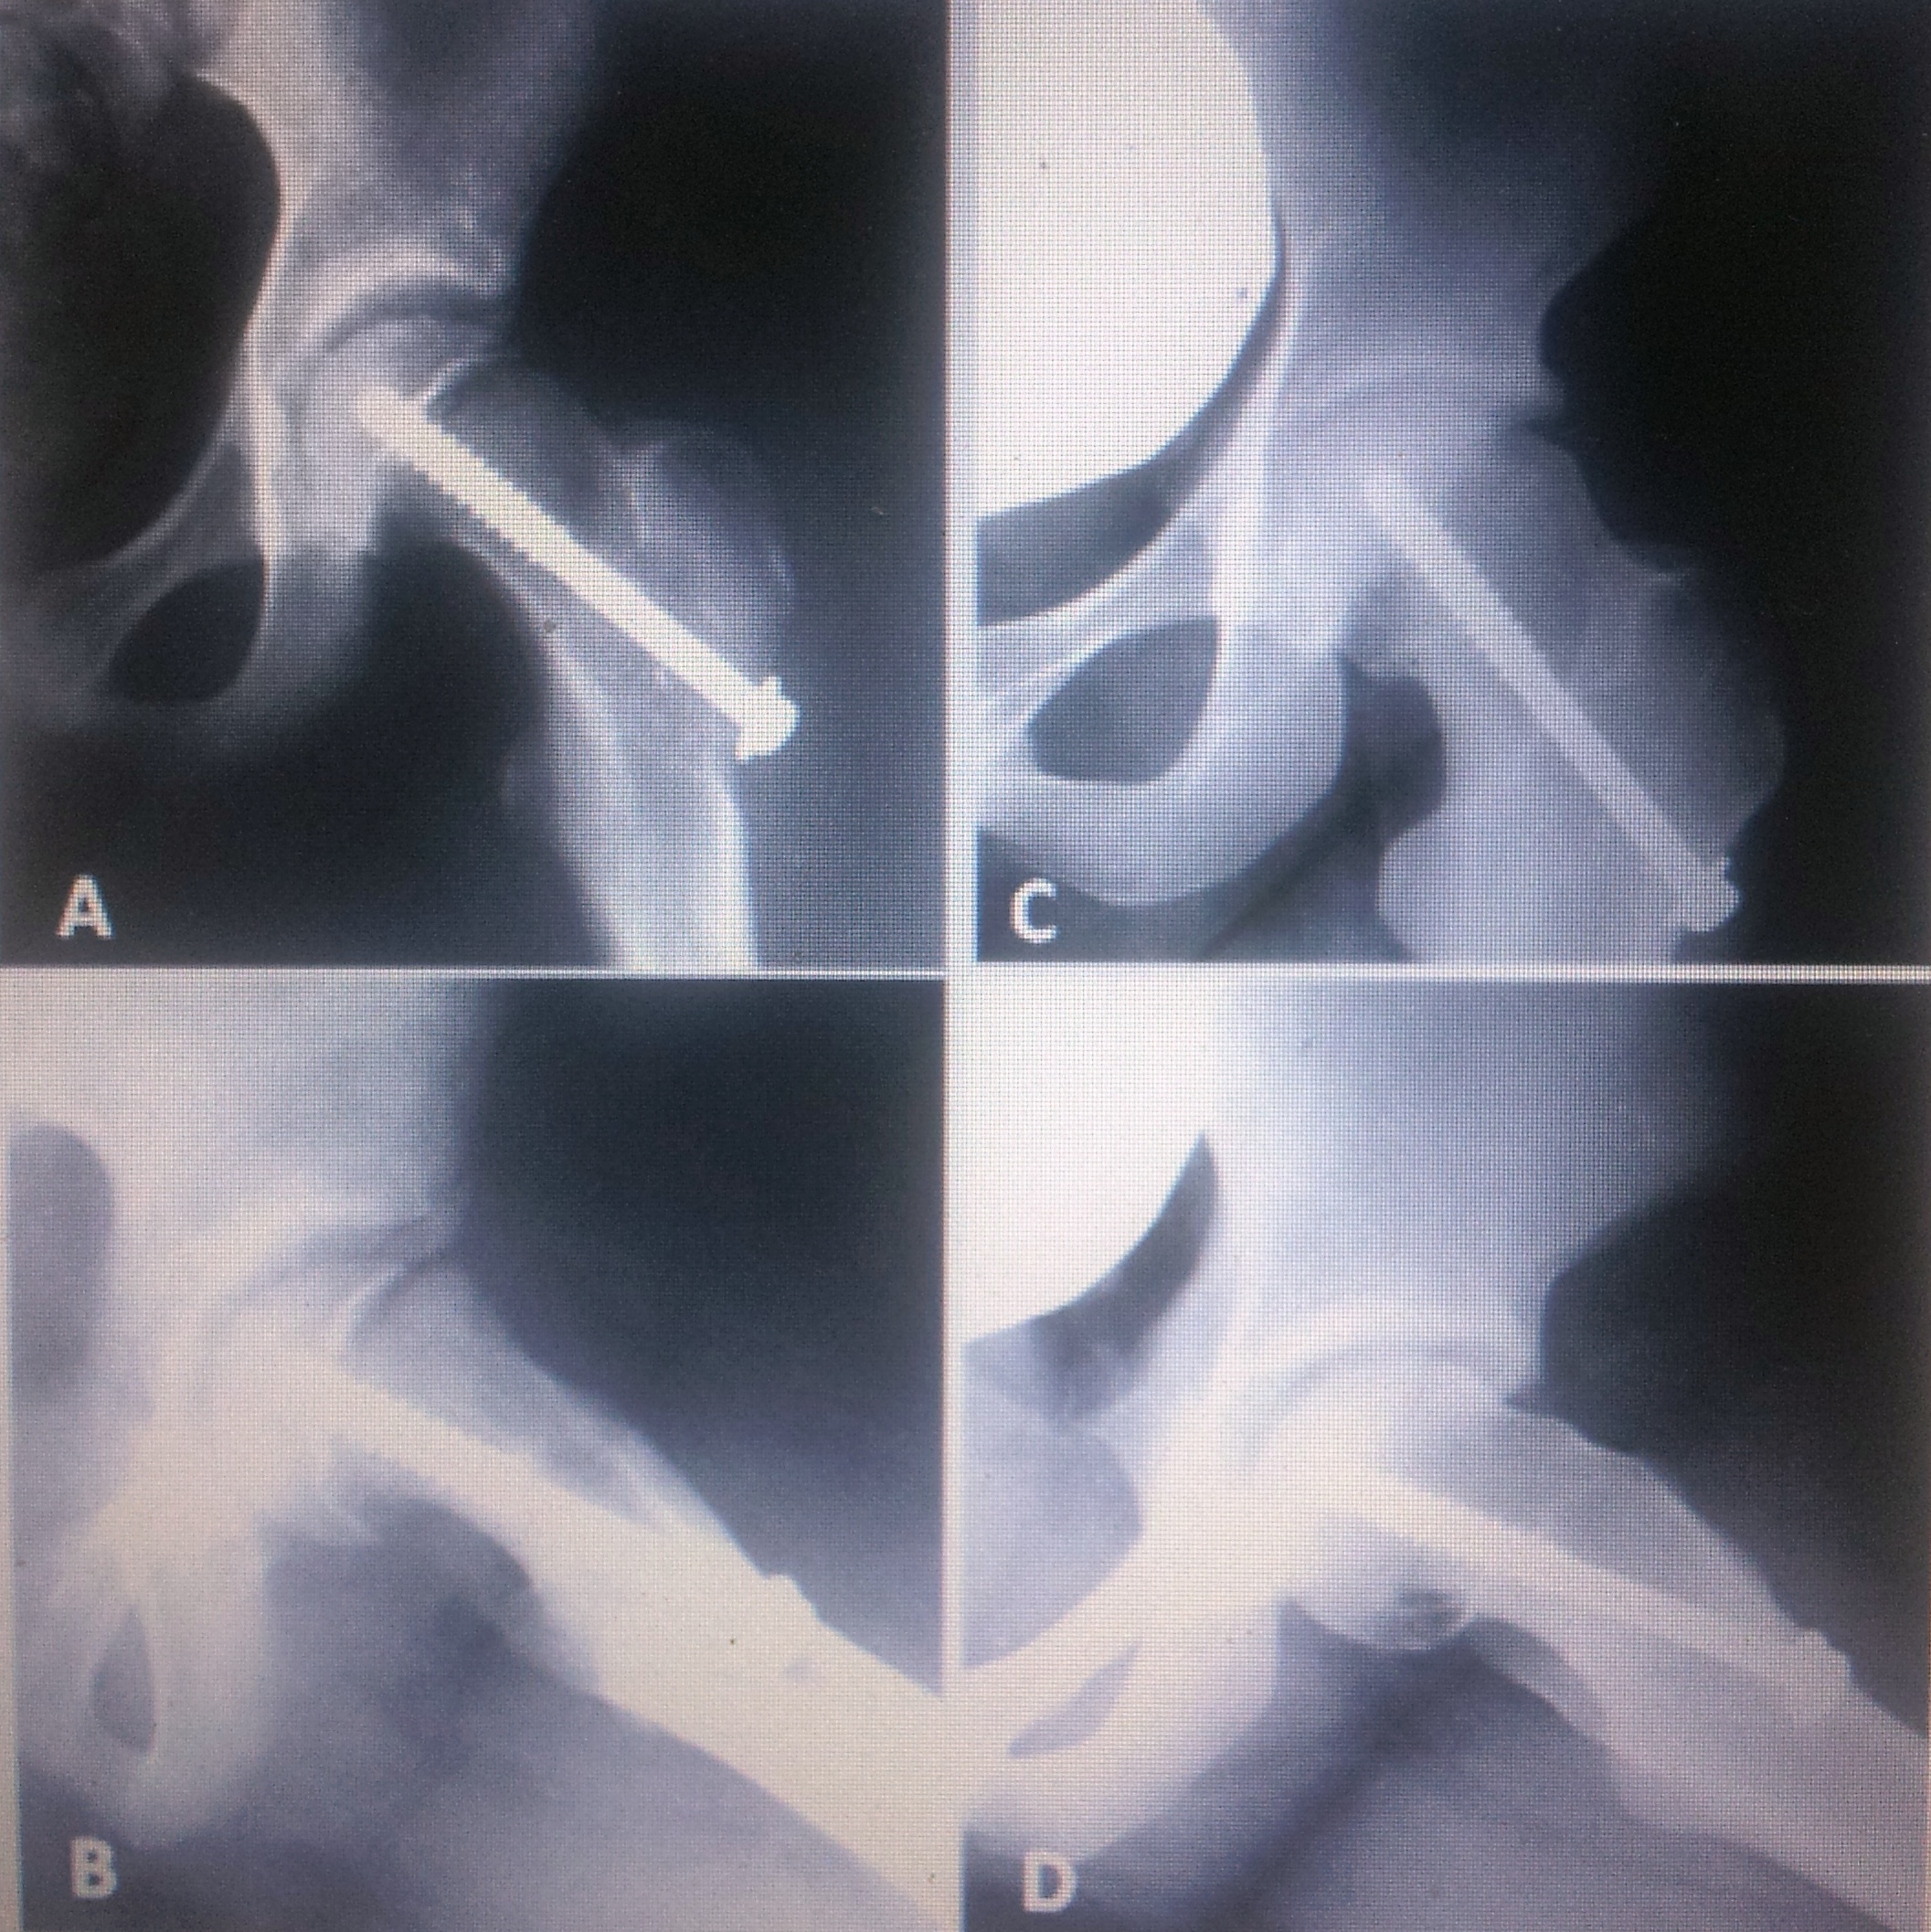

Remodelación y deterioro en epifisiólisis de cadera después de la fijación in situ. [Slipped capital femoral epiphysis remodeling and deterioration after in situ fixation]